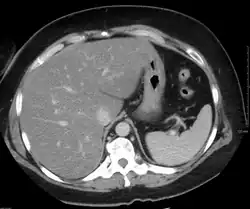

Liver steatosis (fatty liver disease) as seen on CT

Imaging studies are often obtained during the evaluation process. Ultrasonography reveals a "bright" liver with increased echogenicity. Medical imaging can aid in diagnosis of fatty liver; fatty livers have lower density than spleens on computed tomography (CT), and fat appears bright in T1-weighted magnetic resonance images (MRIs). Magnetic resonance elastography, a variant of magnetic resonance imaging, is investigated as a non-invasive method to diagnose fibrosis progression.[27] Histological diagnosis by liver biopsy is the most accurate measure of fibrosis and liver fat progression as of 2018.[6]